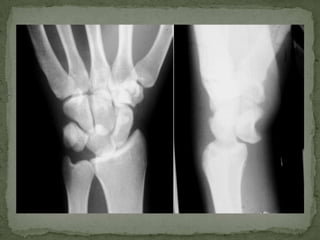

A 65-year-old female presented to the emergency department with right hand pain after falling down stairs. On examination, she had swelling of the right hand with limited motion of the wrist and hand. She was diagnosed with a lunate dislocation of the right wrist which requires emergent orthopedic consultation and may need to be repositioned in the emergency department or operating room. Complications are common after a lunate dislocation such as arthritis and wrist instability.